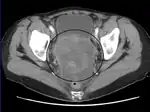

![]() | |

| عکاسی ریزنگاری از یک تومور سرطان تخمدان | |